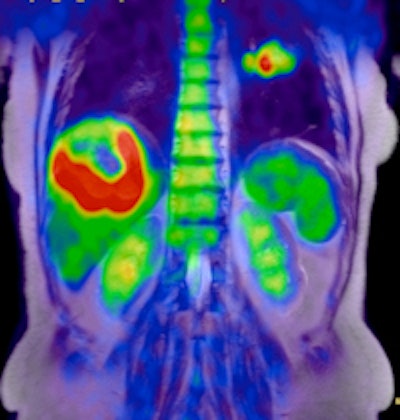

PET/MR image acquired on Ingenuity TF indicates liver tumor.

Philips is highlighting the radiation dose reductions possible by using MRI instead of CT as the anatomical modality with PET. In one case, a patient received only 13.6 mSv of total dose in the PET/MRI study, as opposed to 29.6 mSv from a PET/CT exam, in which the CT component contributed 16 mSv of dose.